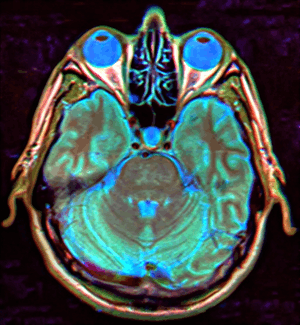

Empty sella syndrome (abbreviated ESS) is where the pituitary gland shrinks or becomes flattened,[1] filling the sella turcica, or "Turkish Saddle", with cerebrospinal fluid on imaging instead of the normal pituitary. ESS can be found in the radiological workup of pituitary disorders, or as an incidental finding when imaging the brain.

MRI scans are useful in evaluating ESS and differentiating it from other disorders that produce an enlarged sella.

The major differential to consider in empty sella syndrome is intracranial hypertension, of both unknown and secondary causes, and an epidermoid cyst, which can mimic cerebrospinal fluid due to its low density on CT scans, although MRI can usually distinguish the latter diagnosis.[2]